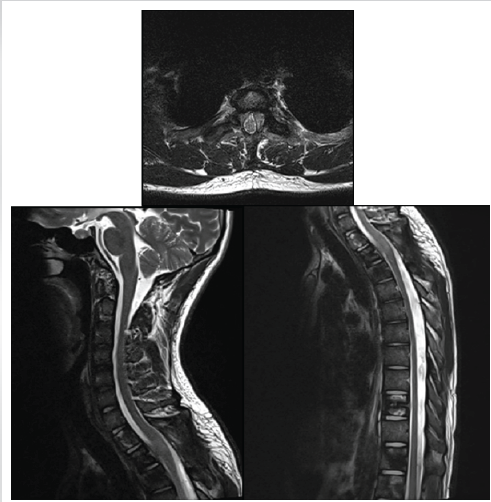

Serial follow-up PET-CT scans showed an initial partial metabolic response after four cycles of cisplatin–etoposide, followed by stable disease with mild metabolic progression after 5 months of therapy. The most recent MRI of the pelvis and whole spine, performed 6 months after initiation of chemotherapy, demonstrated residual enhancing deposits at D1–D2 with additional metastatic lesions in the pelvis and iliac bones, consistent with partial but incomplete response (Fig. 4).

Figure 4: Six-week post-operative magnetic resonance imaging of the dorsal spine showing adequate decompression of the spinal cord at the D1–D2 level with resolution of cord compression and myelopathic changes. Mild post-operative enhancing soft tissue is seen along the posterior margin.